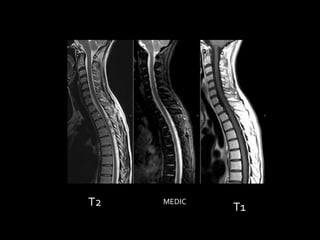

T2   MEDIC

T1

T2 MEDIC T1

SECUENCIAS Y TIEMPOSDE RELAJACIÓN  Todos los estudios deben incluir imágenes potenciadas en T1 y T2 al menos en dos planos del espacio  En cada secuencia, ya sea potenciada en T1 o T2, la escala de grises cambia y es totalmente diferente a las densidades radiológicas vista en Tc o Rx simple.  La diferencia entre unas secuencias y otras depende del tipo de pulsos de radiofrecuencia utilizados y del tiempo que hay entre ellos.

SECUENCIAS  Secuencias T1:muy buena correspondencia anatómica, pero poco sensibles a los cambios patológicos  Secuencias T2: muy sensibles a cambios patológicos, pero no demuestran tan bien la anatomía. (requiere + tiempo)  Como la mayoría de cambios patológicos son inflamatorios o tumorales, comportan cambios de edema (aumento de agua en los tejidos). Como en T2 agua es blanca, la mayoría de lesiones serán hiper-intensas en T2